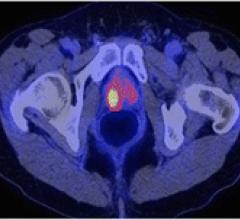

Siemens' PETNET Solutions, a wholly owned subsidiary of Siemens Healthcare, announced it will provide clinical researchers in the greater New York City area with access to gallium-68-labeled prostate-specific membrane antigen (Ga-68 labeled PSMA). This investigational tracer is being studied for prostate cancer imaging using positron emission tomography/computed tomography (PET/CT) in clinical trials throughout the world.